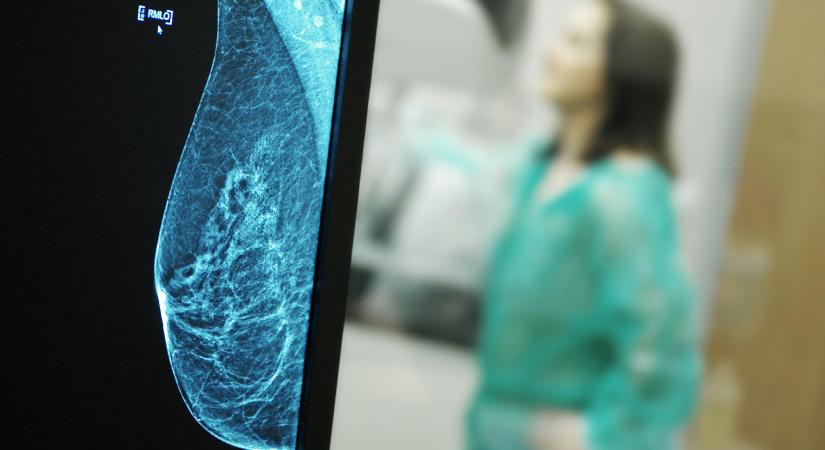

Az onkológia rákfenéje a betegút – mondja Szántó István onkológus, aki 46 éves praxisa során sem tudta megszokni a rák gonoszságát. Hogyan közli a diagnózist? Miért maradhat sok eset ellátatlanul? Miért elhibázott a mellrákszűrés protokollja Magyarországon Újhelyi Mihály plasztikai sebész szerint? Milyen, amikor a páciens mosollyal távozik az emlőrekonstrukció után? Az onkológussal és a plasztikai sebésszel a hajlamosító génmutációkról és a különféle szűrési lehetőségekről is beszélgettünk.